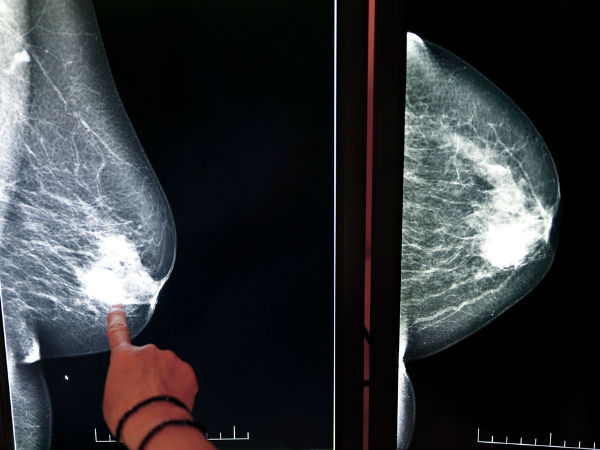

ब्रेस्ट कैंसर के लक्षण क्या हैं?

विश्व स्तर पर सबसे अधिक कैंसर फेफड़े, स्तन और कोलोरेक्टल के पाए जाते हैं। सामान्यत: ब्रेस्ट कैंसर के कोई विशिष्ट लक्षण नहीं होते। संकेतों की अस्पष्टता होने के कारण इसका पता लगाना मुश्किल होता है।

स्तन में गाँठ होना, निप्पल से खून आना, निप्पल में गड्ढा पड़ना, निप्पल में खिंचाव, छाती की रूपरेखा में बदलाव, निप्पल पर रैश आना, ये सभी चिंता का कारण हो सकते हैं। सबसे प्रमुख लक्षण छाती में गाँठ आना है।

वास्तव में छाती में आने वाली हर गाँठ खतरनाक नहीं होती। स्तन में होने वाली लगभग 10 प्रतिशत गांठें ही कैंसर की होती हैं।